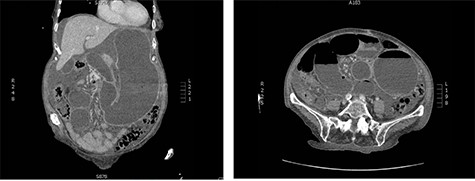

An 83-year-old female presented to the emergency room with epigastric abdominal pain, nausea and vomiting for 1 day. She has a history of recurrent midgut volvulus for which she underwent two exploratory laparotomies in the prior 2 months, most recently, 3 weeks prior. In those operations, the patient was found to have an abnormally elongated small bowel mesentery which was torsed in a clockwise fashion. The mesentery was detorsed in both operations and no bowel resections nor pexy were performed. The operations were done open due to significant bowel distension and concern for potential bowel injury with a laparoscopic approach. She was recovering well from prior detorsion when she developed sudden onset nausea and vomiting 1 day prior to presentation. She also had not passed any flatus or bowel movements for the past 2 days. The patient’s past medical history was significant for Crohn’s disease, hypothyroidism and hypertension. She was recently diagnosed with Crohn’s but had not yet initiated treatment for it. She had no prior abdominal surgical history other than the recent exploratory operations. Computed tomography (CT) abdomen/pelvis obtained in the emergency room demonstrated gastric distension, swirling of the small bowel mesentery and ascites, concerning for small bowel obstruction secondary to recurrent midgut volvulus (Fig. 1). A nasogastric tube was inserted for decompression and the patient was emergently taken to the operating room for exploration and reduction of the volvulus.

CT abdomen and pelvis on presentation; swirling of the SMA, markedly distended stomach and small intestine are noted.